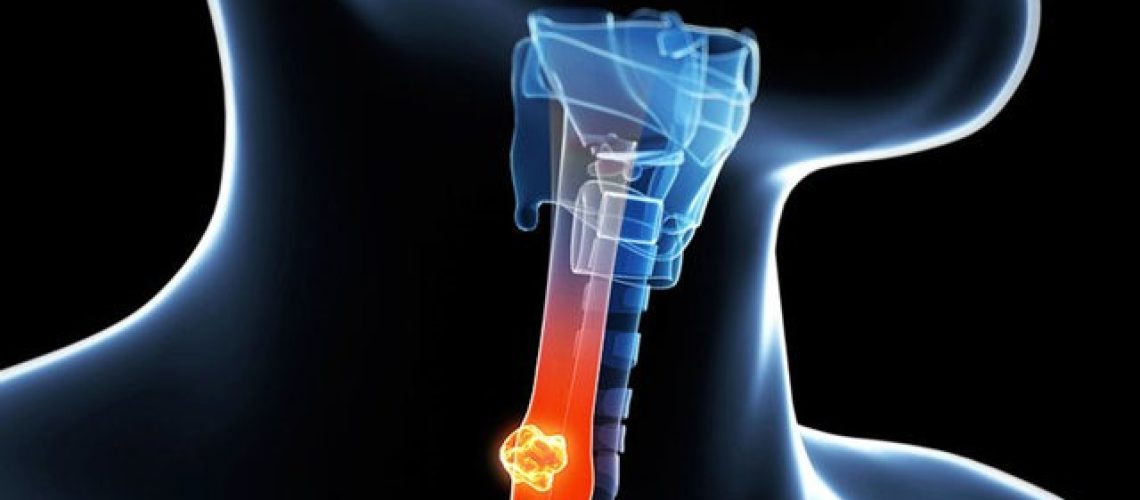

یک نکته حائز اهمیت در مورد سرطان حلق این است که این نوع سرطان ممکن است در بخشهای مختلفی از گلو ایجاد شود، که به همین دلیل انواع گوناگونی دارد. حلق با طول حدود شش اینچ، از پشت گلو تا ابتدای مری امتداد دارد. این ساختار اصلی شامل:

- نازوفارنکس (بخش پشتی حفره بینی)

- اوروفارنکس در پشت حفره دهان (کام نرم)

- حنجره (که به مری منتهی میشود)

این بخشها با غشاهای مخاطی، بافت هم بند، غدد، بافت لنفاوی، و ماهیچههای پشت حلق تشکیل شدهاند. همگی این اجزا ممکن است به سرطان مبتلا شوند.